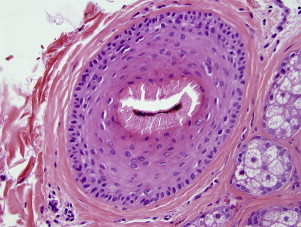

Tufting as a Clue to Neutrophil-Mediated Scarring Alopecia

Large tufts of hair protruding from a common infundibulum (“six-packs” or “doll’s hair”) can be a clue to the quiescent phase of neutrophilic forms of alopecia, especially folliculitis decalvans and acne keloidalis nuchae ( Fig. 3 ). Lymphocyte-mediated forms tend to produce smaller clusters of hairs. Large tufts can also be seen after burns and as physiologic tufting, especially in the occipital scalp, so the finding of six-packs must be interpreted in the context of the clinical presentation.